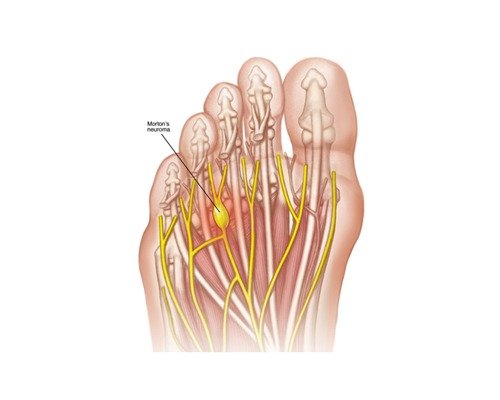

La Sindrome di Civinini Morton (Italia 1835), meglio nota come Neuroma di Morton, é causata dall’apposizone di tessuto fibroso a livello del nervo interdigitale nel tentativo del nostro corpo di difendersi dalla compressione delle ossa metatarsali.

Può causare dolore, difficoltà alla deambulazione e perdita della sensibilità alle dita dello spazio interessato.

Nella quasi totalità dei casi é presente tra il terzo e il quarto metatarso.

Il trattamento chirurgico per il Neuroma di Morton è spesso considerato quando i rimedi conservativi, come plantari, terapia fisica o infiltrazioni, non portano risultati soddisfacenti.

Nel dettaglio é possibile eseguire:

La chirurgia può portare a un notevole miglioramento della qualità della vita, ma come ogni intervento, presenta rischi e benefici. È fondamentale discutere tutte le opzioni con un chirurgo specializzato e scegliere la migliore per la propria situazione.